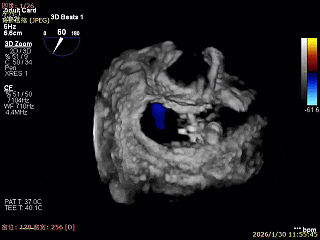

3D Enface下组织桥稳定残余外侧前叶脱垂

3D Enface上彩可见夹子内侧无反流,残余外侧反流